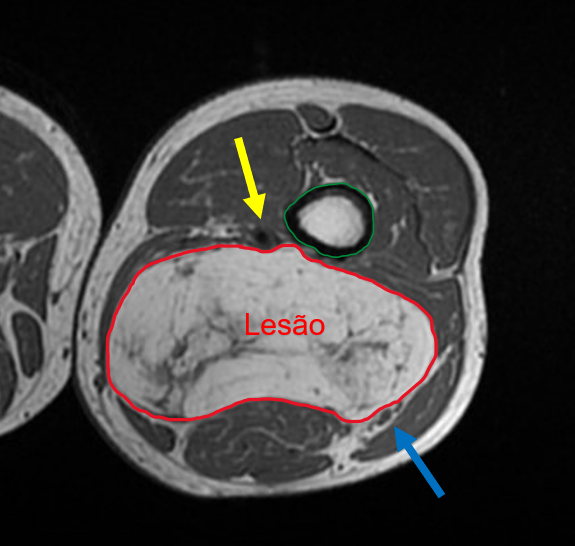

Você acompanha um caso, de um paciente de 70 anos, do sexo masculino, com abaulamento na região posterior da coxa há 6 meses, com crescimento progressivo. Este paciente já realizou exames de imagem, que constataram uma lesão com conteúdo de gordura em meio à musculatura da coxa, com diagnóstico presuntivo de lipossarcoma.

Mesmo com o diagnóstico presuntivo em mãos, uma ressonância magnética foi solicitada, para planejamento pré-operatório. Como cirurgião do caso, é fundamental que você compreenda a relação deste tumor com as estruturas adjacentes, com o objetivo de planejar o seu procedimento.

Nesta imagem de ressonância magnética da coxa, temos a lesão sugestiva de lipossarcoma (circundada pela linha vermelha), localizada em meio à musculatura da região posterior da coxa. Esta lesão desloca as estruturas musculares adjacentes e, apesar de apresentar proximidade, não invade o fêmur (circundado pela linha verde). A lesão faz contato com os vasos femorais superficiais (seta amarela) e com o nervo ciático (seta azul), porém sem sinais de invasão.

De posse das informações trazidas pelo exame, o seu procedimento cirúrgico será mais assertivo. Você iniciará a ressecção deste tumor sabendo quais estruturas invade e com quais estruturas nobres (vasos e nervos) faz contato.